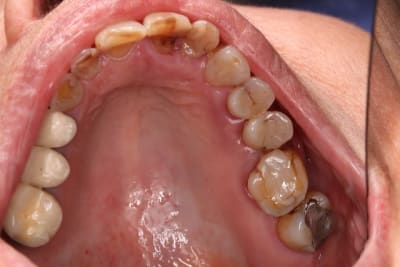

Bon pour le haut ça va être traitement CCAM à base de couronnes.

Le bas, on garde ou on vire ? 34 mobile, le reste ça bouge pas.

Jusqu'à la photo 3 j’étais pour le traitement CCAM (disque diamanté+foret + empreinte.... nan je déconne pas le disque... humm ...nan).

Au vu de la photo 4 le plan de traitement est purement verbal:

"Votre cas est trop complexe pour moi, allez à la ville ya plein de cador moi je fait que les cas facile." Vu qu'il portera peut-e^tre pas son stéllite ( CCAM toujours) j'aurais trop peur pour mes cerams.

Oui , aller,,on garde le bas qui nous servira de repère pour faire le haut

Je garderai tout ce qui ne bouge pas en bas. Virer des dents immobiles et asymptomatiques c'est sévère ! ;) Un bon bloc d'ancrage pour le stellite.

Pour moi l'usure en haut est purement mécanique.

ah ben non pas chimique non plus , la mamie , elle grignote avec les quenottes de devant , tel un petit lapin ! parce qu'elle a plus rien derrière ... faut pas lui enlever ses dents ....et refaire en sorte qu'elle se serve des molaires ... j'ai bon là Enlaye ?

Pour le haut, je reste sur mon idée d'érosion, même si ça change les paramètres de collage, on s'en fout un peu au final.

Heuuu , t'as des dents usées pile poil en face de dents naturelles, elles mêmes usées et tu nous parles d'érosion chimique avec preuve l'appui ? faut sortir la tête des bouquins et ouvrir un peu les yeux ! Et t'as intérêt d'en tenir compte à mon avis ...Maintenant qu'elle sirote du jus de citron pourquoi pas mais la cause principale est mécanique !